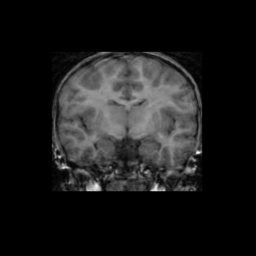

Test/Retest Reliability

FSL was run on each scan in the Brain Segmentation Testing Protocol (BSTP) between-scanner test/retest dataset. Select a subject below to see volumes for each subject across the subject's scans.